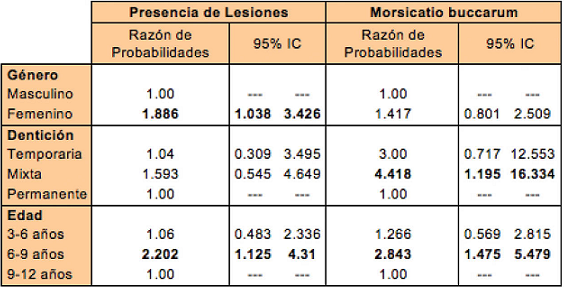

Se realizó un análisis de regresión logística para determinar la relación entre el género, el tipo de dentición y la edad con las lesiones de las mucosas bucales para la muestra. Se calcularon también las razones de probabilidades (odds-ratio) para las variables consideradas en el estudio. Como Morsicatio buccarum fue la única lesión que produjo diferencias significativas en 2 de las 3 variables, se procedió a realizar un análisis de regresión logística con cálculo de razones de probabilidad para dicha entidad.

La tabla 5 muestra los resultados de la regresión logística y las razones de probabilidad.

El género, edad y tipo de dentición estuvieron estadísticamente asociados con las lesiones de mucosa bucal en esta muestra. Las niñas tuvieron 1.886 veces mayor probabilidad de presentar algún tipo de lesión que los niños (95% IC: 1.038-3.426). El rango de edades de 6-9 años tuvo 2.202 veces mayor riesgo de presentar algún tipo de lesiones comparado con el grupo de 9-12 años (95% IC: 1.125-4.31). Los sujetos con dentición mixta tuvieron 4.418 (95% IC 1.195-16.334) veces más riesgo de presentar la lesión Morsicatio buccarum comparados con el grupo de dentición permanente. Asimismo, los individuos de 6-9 años tuvieron 2.843 mayores posibilidades de presentar Morsicatio buccarum que el grupo de 9-12 años (95% IC: 1.475-5.479).

Las niñas tuvieron 1.886 veces mayor probabilidad de presentar algún tipo de lesión que los niños (95% IC: 1.038-3.426). El rango de edades de 6-9 años tuvo 2.202 veces mayor riesgo de presentar algún tipo de lesiones comparado con el grupo de 9-12 años (95% IC: 1.1254.31). Los sujetos con dentición mixta tuvieron 4.418 (95% IC 1,195-16,334) veces más riesgo de presentar la lesión Morsicatio buccarum comparados con el grupo de dentición permanente. Asimismo, los individuos de 6-9 años tuvieron 2.843 mayores posibilidades de presentar Morsicatio buccarum que el grupo de 9-12 años (95% IC: 1,475 5,479).